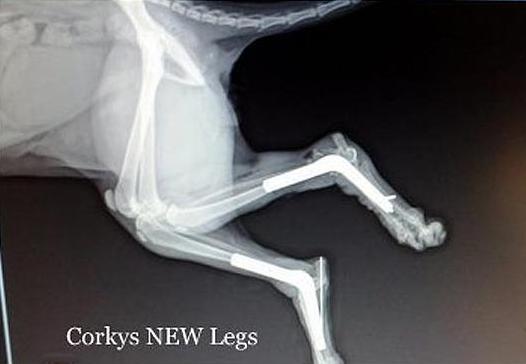

Εθελοντές του κέντρου τον βρήκαν να σέρνεται στους δρόμους της Μινεσότα και τον μετέφεραν στο κέντρο περίθαλψης. Ύστερα από πέντε ώρες στο χειρουργείο τα πόδια του ήταν… στη σωστή τους θέση!

Δυστυχώς όμως το αριστερό του πόδι δεν επουλώθηκε και οι γιατροί αναγκάστηκαν να το ακρωτηριάσουν, αλλά ο Corky δεν το έβαλε κάτω και προσπαθεί να συνηθίσει την καινούρια «κατάσταση».

«Κάνει μικρά βήματα κάθε μέρα. Ένα βράδυ τον είδαμε να τεντώνεται και να στηρίζεται στο πίσω του πόδι. Το δοκιμάζει και κοιτάζει να δει αν μπορεί να αντέξει το βάρος του» είπε ένας υπάλληλος του κέντρου.